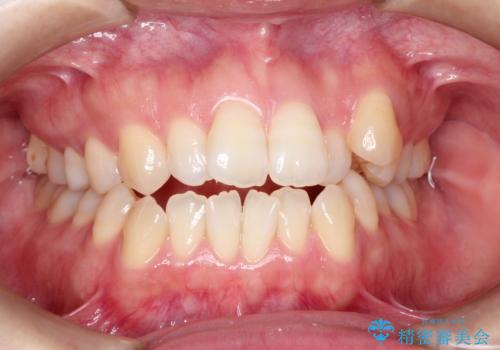

- 前歯のでこぼこが気になると来院されました。

奥歯の噛み合わせは綺麗に噛んでいたため、前歯の叢生(でこぼこ)を、短期間で治療完了するように計画しました。

前歯のガタツキを改善する治療法として、マウスピース矯正が適していることが多いです。

マウスピース矯正は、金属製のブラケットやワイヤーを使用せずに、透明なマウスピースを装着して歯を移動させる方法です。そのため、目立たず、痛みも少ないです。